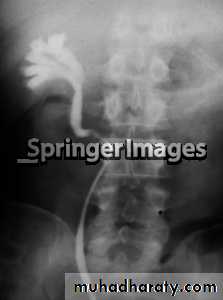

*Cobra head:-rounded or elliptical dilatation of lower end of ureter with thin lineal filling defect around it with proximal dilatation of the rest of ureter.

*Cobra head: rounded or elliptical dilatation of lower end of ureter with thin lineal filling defect around it with proximal dilatation of the rest of ureter